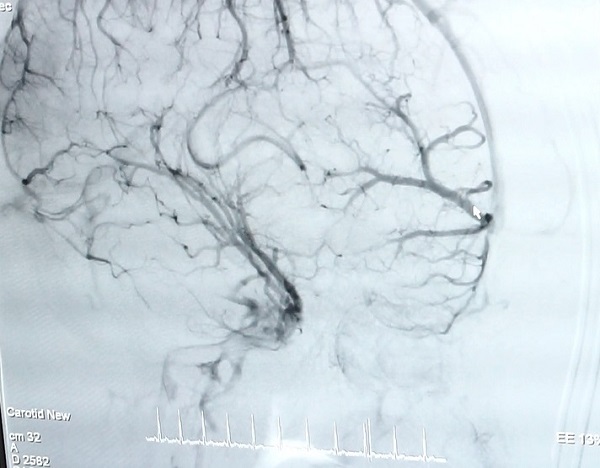

Đau đầu do dị dạng mạch máu não: Diễn tiến đau âm ỉ, dai dẳng, đôi khi phát lên cơn đau lớn có thể kèm theo liệt run. Dị dạng mạch máu não có thể gây ra xuất huyết não, động kinh, nặng có thể hôn mê và tử vong.

Dị dạng mạch máu não là hiện tượng các mạch máu bất thường, rối loạn trong não. Những dị dạng mạch máu này khi vỡ gây chảy máu não. Đây là một căn bệnh bẩm sinh và hết sức nguy hiểm.

Bác sĩ Trần Chí Cường cho biết, dị dạng mạch máu não là bệnh bẩm sinh, đây là sự kết nối bất thường giữa động mạch và tĩnh mạch trong cơ thể. Mạch máu não tại khu vực não bộ thường được chia thành nhiều nhánh nhỏ. Đến một điểm nhất định, các mạch máu sẽ phân nhánh thành nhiều mạch nhỏ gọi là mao mạch. Mao mạch có đường kính bằng một tế bào máu, khoảng một phần năm kích thước sợi tóc con người. Bình thường con người có rất nhiều mao mạch, dòng chảy và áp suất bên trong mao mạch rất thấp.